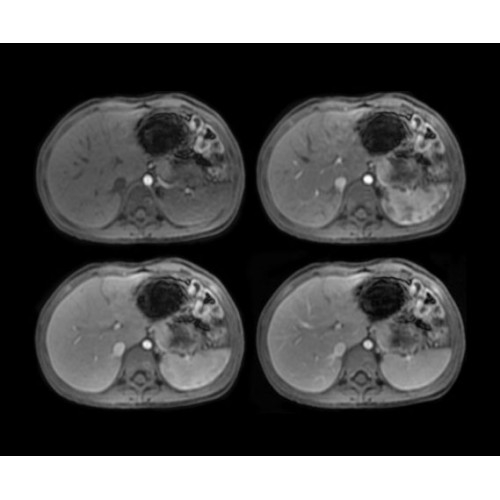

• BodyWorks — для визуализации абдоминальной и тазовой областей, подстраиваясь под запросы пользователя с учетом любых типов пациентов.